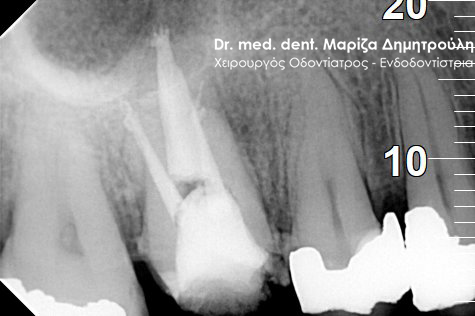

Η ασθενής περιγράφει έναν έντονο συνεχόμενο πόνο στη δεξιά πλευρά της άνω γνάθου που δεν την αφήνει τις τελευταίες μέρες μα εργαστεί. Μετά την κλινική και ακτινογραφική εξέταση της περιοχής διαπιστώθηκε οτι το υπαίτιο δόντι για την πρόκληση των έντονων συμπτωμάτων ήταν ο δεύτερος δεξιός άνω γομφίος, ο οποίος διέθετε ένα παλιό βαθύ σφράγισμα που πίεζε το νεύρο του δοντιού.

Μετά τη χορήγηση τοπικής αναισθησίας αφαιρέθηκε το παλιό σφράγισμα και εντοπίστηκαν οι ριζικοί σωλήνες του δοντιού (βλέπε φωτογραφία). Μετά την κατάλληλη επεξεργασία των ριζικών σωλήνων και εφόσον το δόντι ήταν ασυμπτωματικό η απονεύρωση ολοκληρώθηκε με την έμφραξη των ριζικών σωλήνων με ειδικό εμφρακτικό υλικό.

ΠΡΙΝ

ΜΕΤΑ